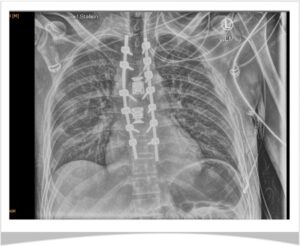

Die Diagnose: Berstungsfraktur, Brustwirbel 4, 5 und 7. Sein Rücken wird in einer ersten Operation sofort notfallmäßig stabilisiert. Eine zweite OP folgt und darauf 3 Monate Reha.